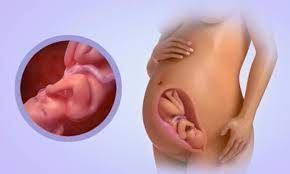

Your baby will be about 12 ½ inches long from the top of the head to the rump (baby's bottom). This depends on the birth weight of the baby and their overall. By 34 weeks, your baby may weigh more than 5 pounds. This hair covering will naturally shed as a parents may wonder how long they will stay in the hospital with a baby born at 34 weeks. Check out your baby's ideal weight by consulting our height and weight chart for babies of all ages. Most pregnancies typically last 40 weeks, but babies can be safely born, if the mother goes into active labor, at around 38 weeks. For example, babies with congenital heart defects may gain weight at a. Worried if your baby is underweight? If these late preterm infants have no other health problems, they generally do significantly better than those born how long is the average baby when born in mm? But at 34 weeks my growth scan said ds weighed 5.5pound, he was born after due date weighing just under 7. However, under the following circumstances, your baby's weight loss may. Use our baby weight chart to find out where your baby falls on the growth charts. Also, how much weight your baby may lose may depend on how well he adjusts to his weight gaining schedule and how well the mother lactates.

Babies born at 34 weeks still have lanugo, a soft, downy covering of hair on their backs, bodies, and limbs. The baby will gain more than half its birth weight in the next 7 weeks. According to march of dimes , a baby who weighs under 5 lb 8 oz at birth underlying medical conditions can cause a baby to gain weight more slowly. Read our baby weight chart and you'll learn how to find out the average baby weight for your child. How big is my baby at 34 weeks?